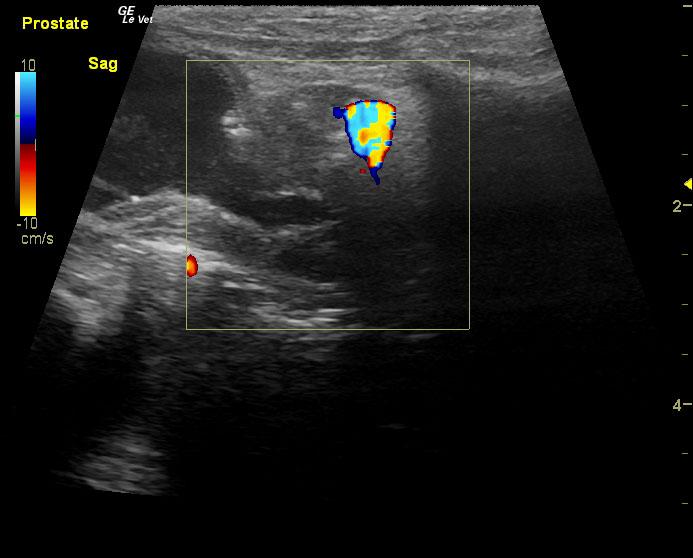

A 14-year-old neutered male Pomeranian dog was presented for evaluation of pollakiuria, diarrhea, inappetence, and lethargy. Abnormalities on physical examination included a painful, enlarged and symmetrical prostate, a very large and firm urinary bladder that could be expressed, and a grade III/VI heart murmur. On survey thoracic radiographs, calcification of the prostate gland was evident.

A 14-year-old neutered male Pomeranian dog was presented for evaluation of pollakiuria, diarrhea, inappetence, and lethargy. Abnormalities on physical examination included a painful, enlarged and symmetrical prostate, a very large and firm urinary bladder that could be expressed, and a grade III/VI heart murmur. On survey thoracic radiographs, calcification of the prostate gland was evident.